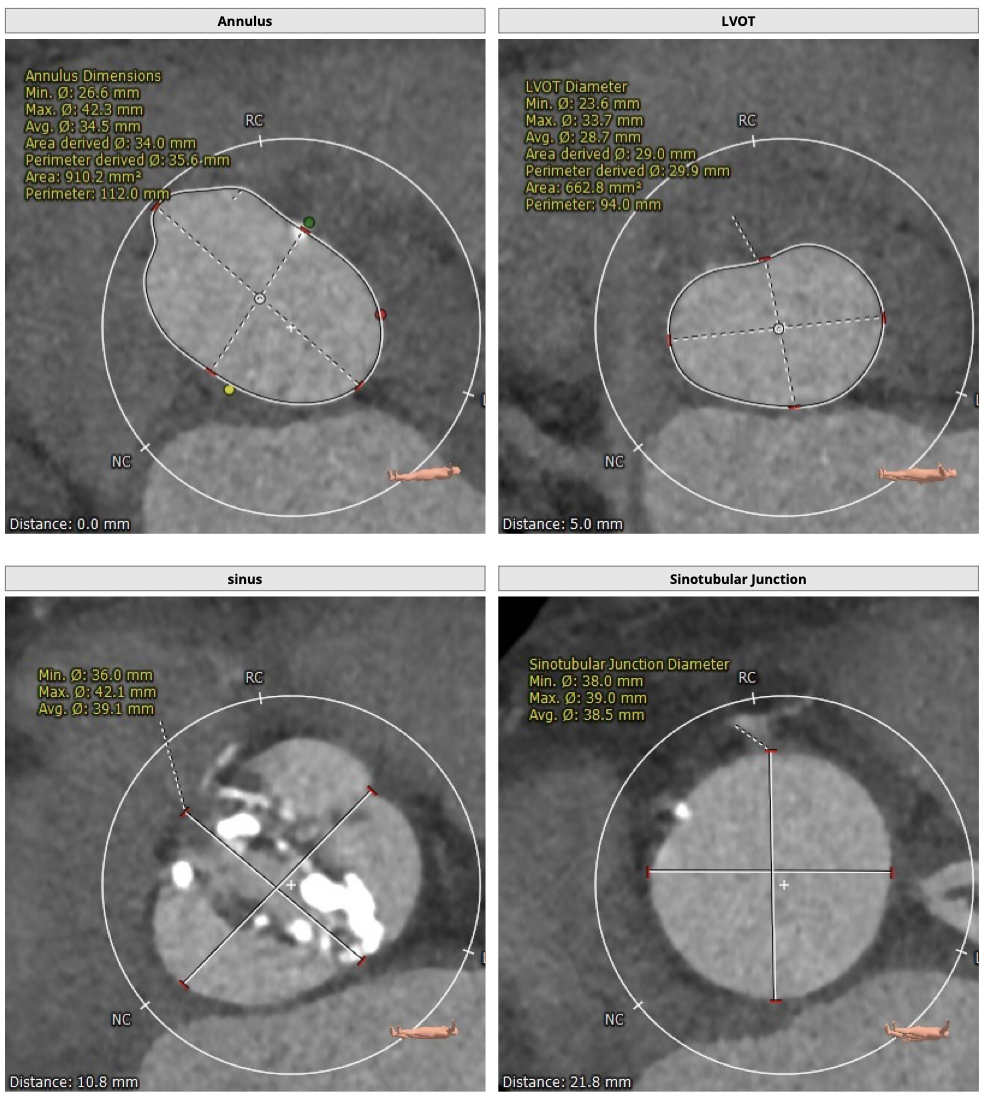

主动脉CT

FEops评估报告

FEops评估瓣周漏

根据FEops量化评估,选用L26瓣膜高位释放会导致8.2ml/s的瓣周漏,而选用L26标准位释放会导致7.4ml/s的瓣周漏,两种释放位置产生的瓣周漏均低于发生中度至重度瓣周漏临界值16ml/s,所以两种释放位置均可以纳入考虑范围,由FEops模拟瓣周漏的3D建模得知发生瓣周漏的主要区域为左右交界处的钙化位置。

L26号瓣膜标准位释放

L26号瓣膜高位释放

FEops评估瓣膜稳定情况

根据FEops评估的L26瓣膜标准位释放结果,发现瓣膜起始位置与稳定位置有较大的改变,判断发生下滑可能性比较大,建议使用VenusA-Plus®可回收输送系统保障手术安全。